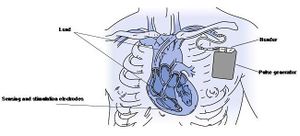

Implantation

Pacemaker implantation is performed under local anaesthesia in a sterile operating room or catheterization laboratory. Implantation starts with inserting the pacemaker lead(s), most often into the left or right cephalic vein. Fluoroscopy is used to ensure the appropriate location in the atrium or ventricle. Leads are often positioned in the auricle of the right atrium and/or the right ventricular apex.

If these tests are within limits, the pacemaker leads are properly positioned. Thereafter, the pacemaker pulse generator is implanted subcutaneously or subpectorally under the left or right clavicle.